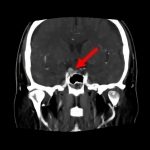

断層撮影

手術前1